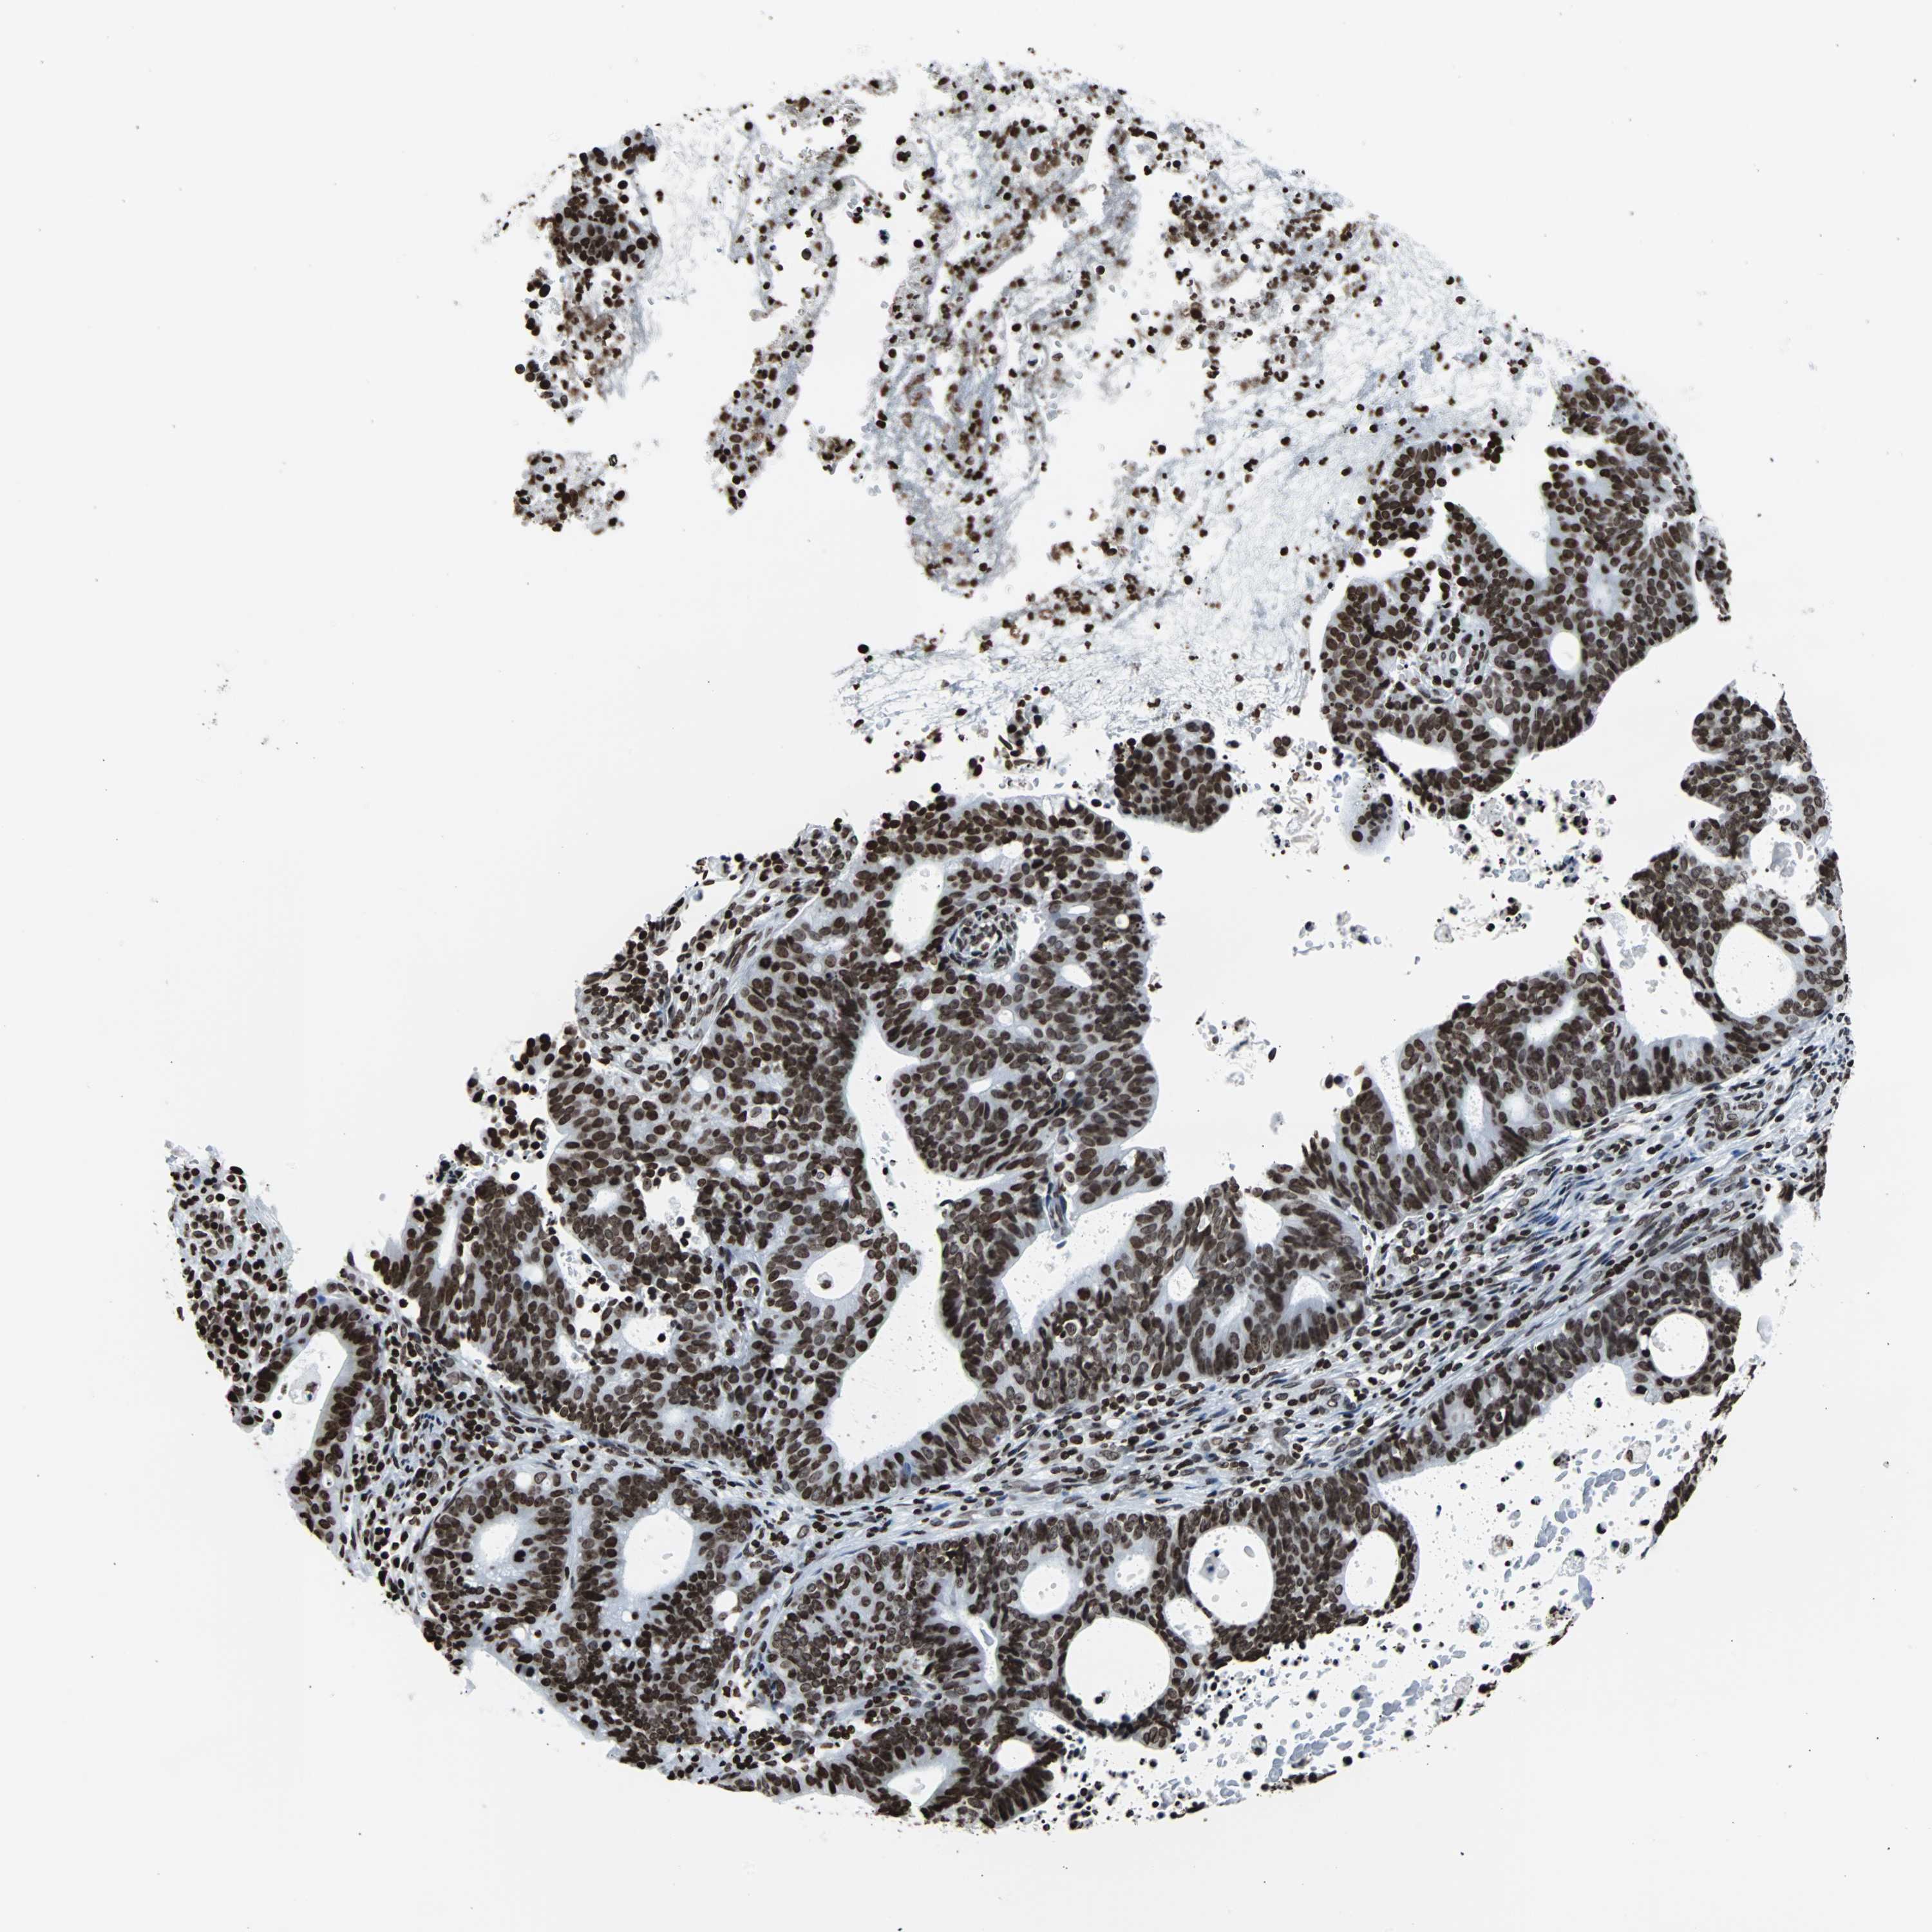

ENDOMETRIAL CANCER - Protein expressioni

A mouse-over function shows sample information and annotation data. Click on an image to view it in a full screen mode. Samples can be filtered based on level of antibody staining by selecting one or several of the following categories: high, medium, low and not detected. The assay and annotation is described here.

Note that samples used for immunohistochemistry by the Human Protein Atlas do not correspond to samples in the TCGA dataset.

Antibody stainingi

Antibody staining in the annotated cell types in the current human tissue is reported as not detected, low, medium, or high, based on conventional immunohistochemistry profiling in selected tissues. This score is based on the combination of the staining intensity and fraction of stained cells.

Each image is clickable and will lead to virtual microscopy that enables deeper exploration of all samples and also displays staining intensity scores, fraction scores and subcellular localization as well as patient and tissue information for each sample.

Antibody HPA042205

Antibody HPA043013

Antibody HPA048671

Antibody CAB007814

Staining

High

Medium

Low

Not detected

Intensity

Strong

Moderate

Weak

Negative

Quantity

>75%

75%-25%

<25%

None

Location

Nuclear

Cytoplasmic/membranous

Cytoplasmic/membranous,nuclear

Adenocarcinoma, NOS